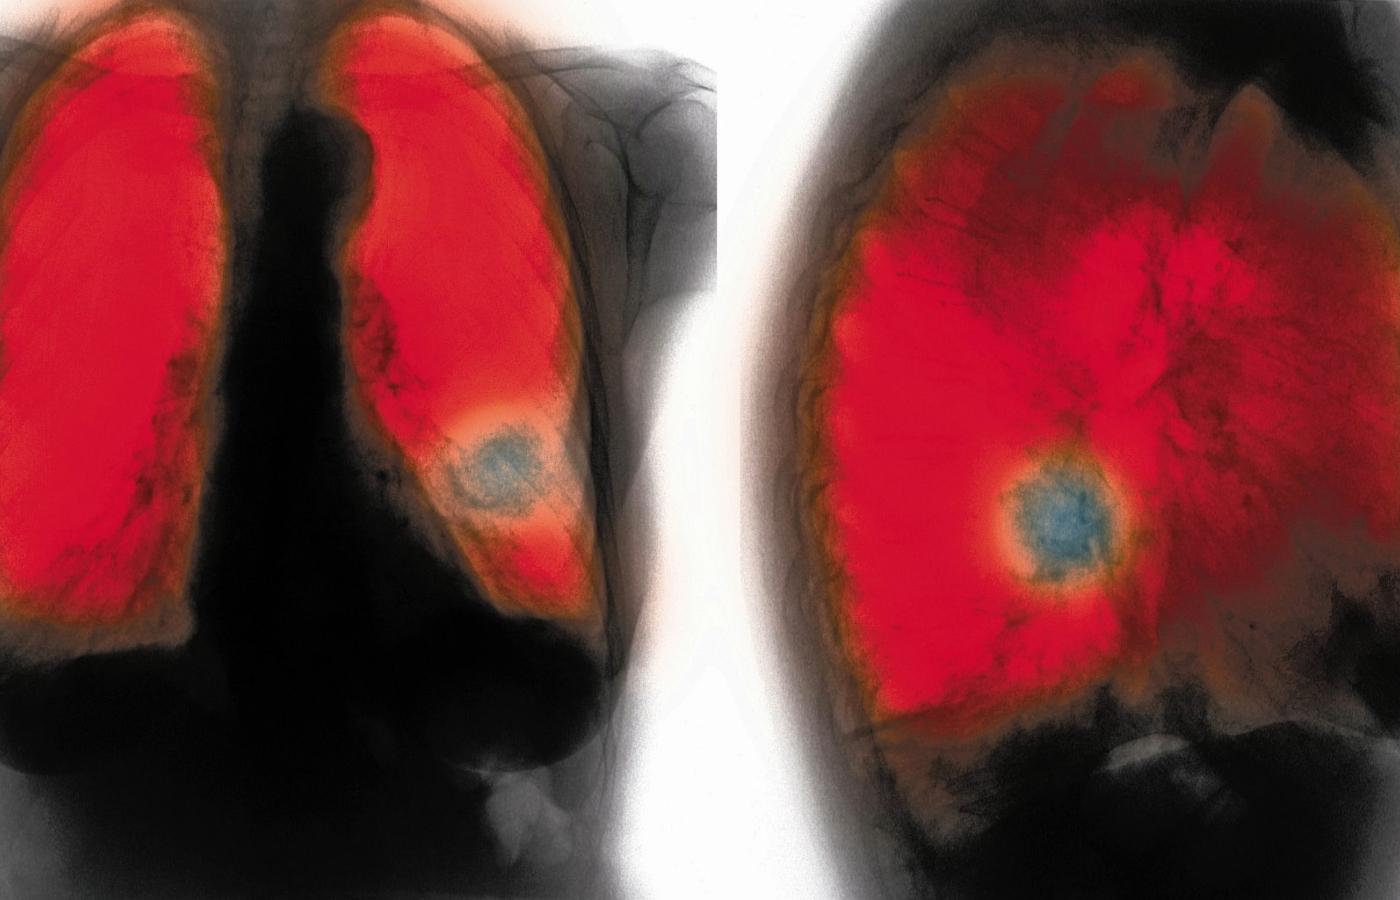

Obraz płuc 76-letniej palaczki papierosów. Zmiany w lewym płucu wskazują na POChp. Obraz płuc 76-letniej palaczki papierosów. Zmiany w lewym płucu wskazują na POChp. FPM / Getty Images/FPM